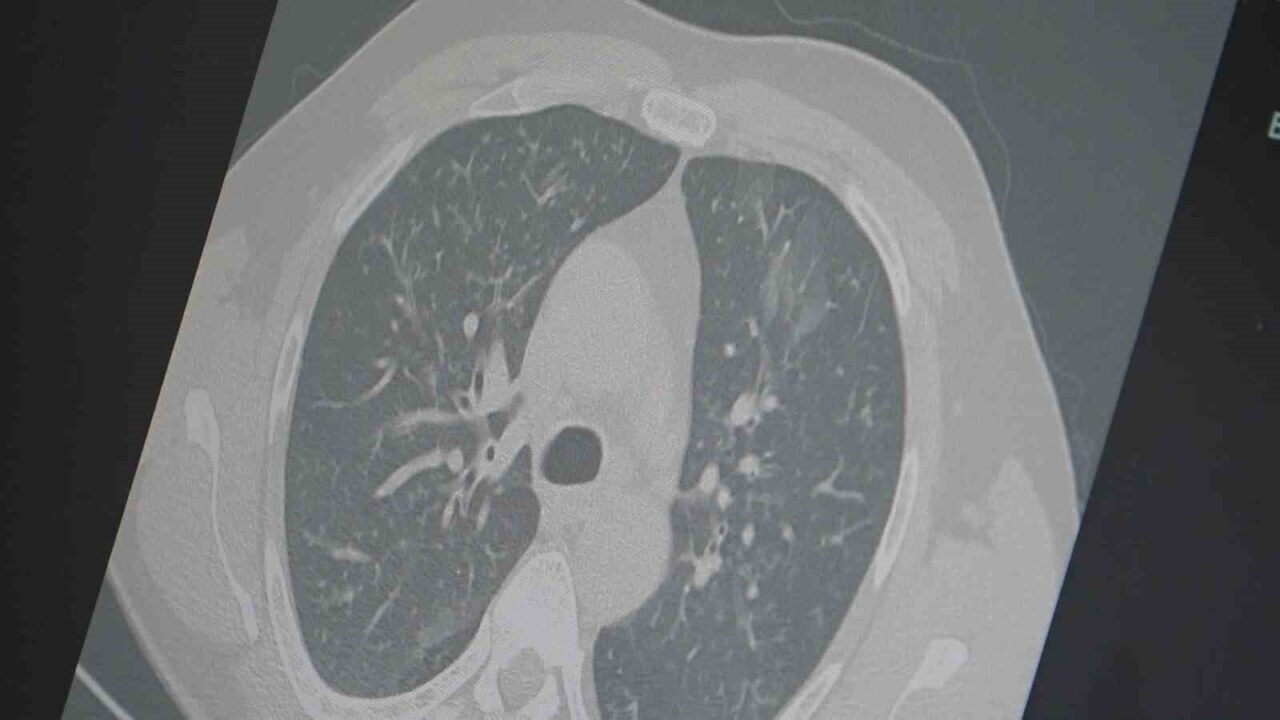

Grip ve Covid-19’un zatürreye dönüşebilme potansiyeline dikkat çeken Dr. Özkaya, “Grip veya Covid sonrası, birçok hasta akciğerlerinde sorunlar yaşıyor ve bu durum zatürreye yol açıyor. Hastaneye yatan hastaların sayısında bir artış gözlemleniyor” ifadelerini kullandı.

Prof. Dr. Özkaya, toplum üyelerine şu tavsiyelerde bulundu: “En ufak grip benzeri belirtileri hisseden bireylerin evlerinde dinlenmeleri gerekmektedir. Uzun süreli öksürük ve nefes darlığı yaşayanların derhal bir doktora başvurarak akciğer röntgeni çektirmeleri ve uygun tedaviyi almaları önemlidir.”